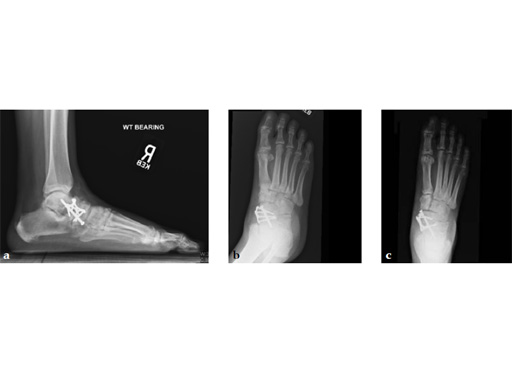

Case 2: First MTP fusion plate

A 38-year-old man presented for opinion after two attempts to fuse the big toe MTP joint. The AP view is significant for luscency at the joint line. The lateral view is notable for loosening of the hardware and malposition because of the dorsiflexion built in to the precontoured implant. Revision was planned using a 0 variable angle locking/compression hallux MTP plate.

At 10 weeks postoperatively (see Fig. 2ab) the patient had no pain with weight bearing. The lateral view demonstrates improved position of the toe using a 0angle plate.